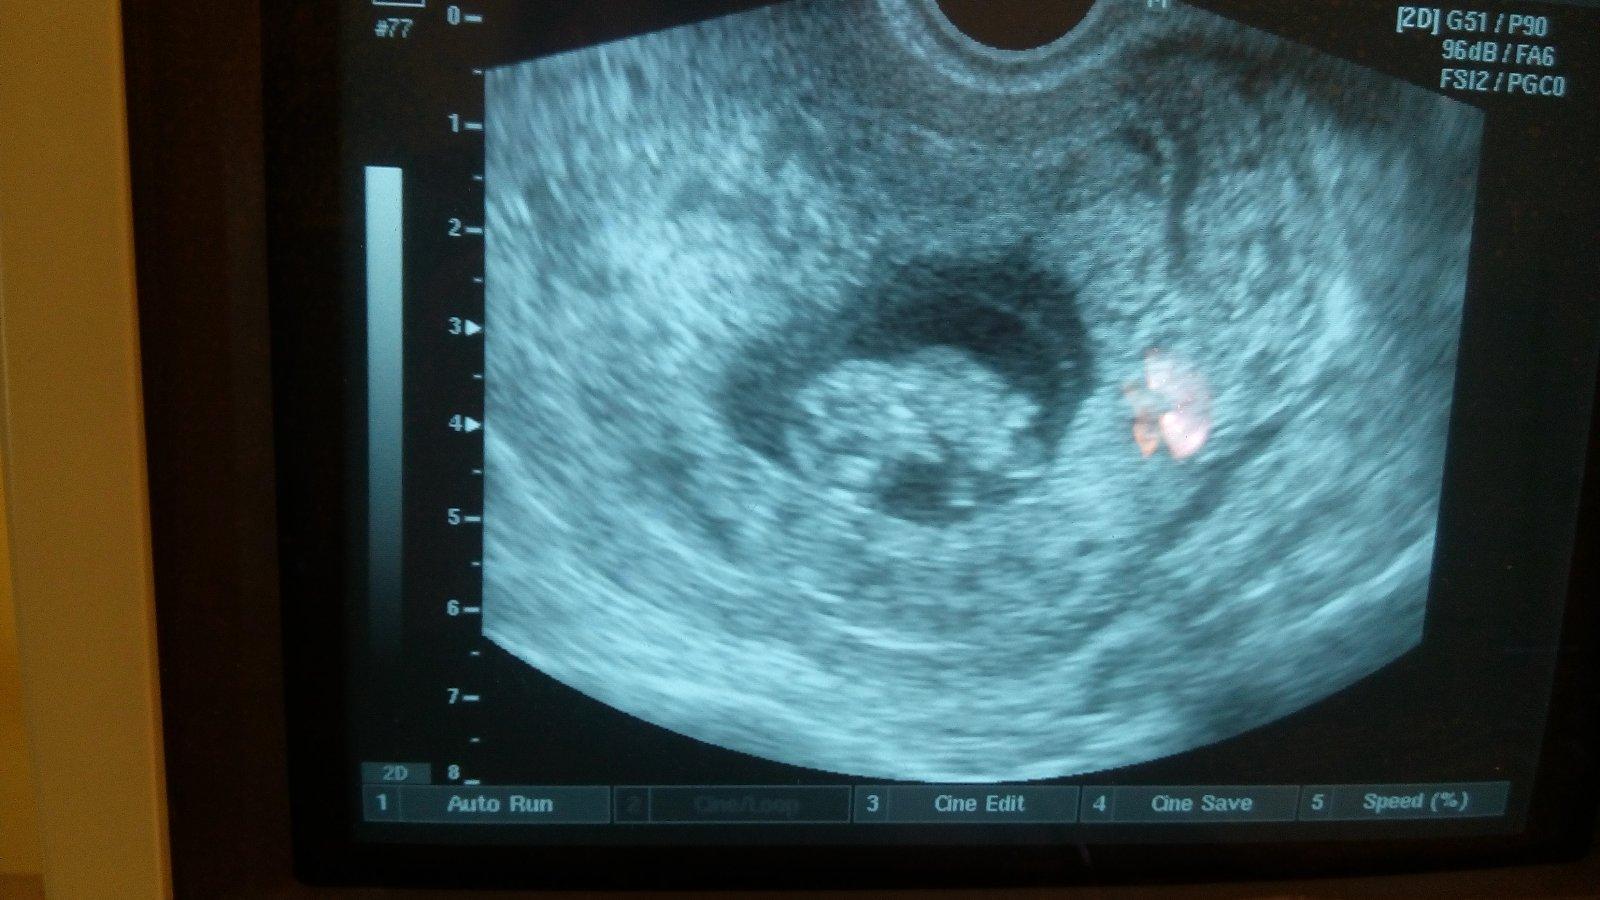

V 10/1 týždni srdiečko bije, pupocnik sa hýbe... Všetko tak ako má byť 🙂 som šťastná veľmi a dnes som sa objednávala na sono v 12 týždni. Ako sa dnes cítite vy?

Ahojte Julovky, pridávam sa k Vam, aj ja som bola vcera na sono a som v 10 tt, všetko je ok malinké som videla bilo mu srdiečko a hýbalo sa. Je to prekrásny pocit :* 30 dec. Idem na 3D ultrazvuk 🙂 do KE

Ahojte dievčatá 🙂 tak odbery v 10 týždni za nami aj sono babo krásne dnes sme